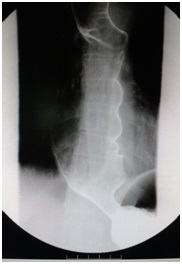

术前(食管中下段管腔明显扩张,贲门呈鸟嘴样狭窄) POEM术后(贲门开放良好)